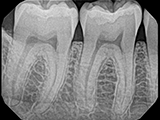

| X-Ray Example |

X-ray taken with the Dexis Sensor |

Dental X-Ray Comparison

X-ray taken with the Dexis™ sensorSchick